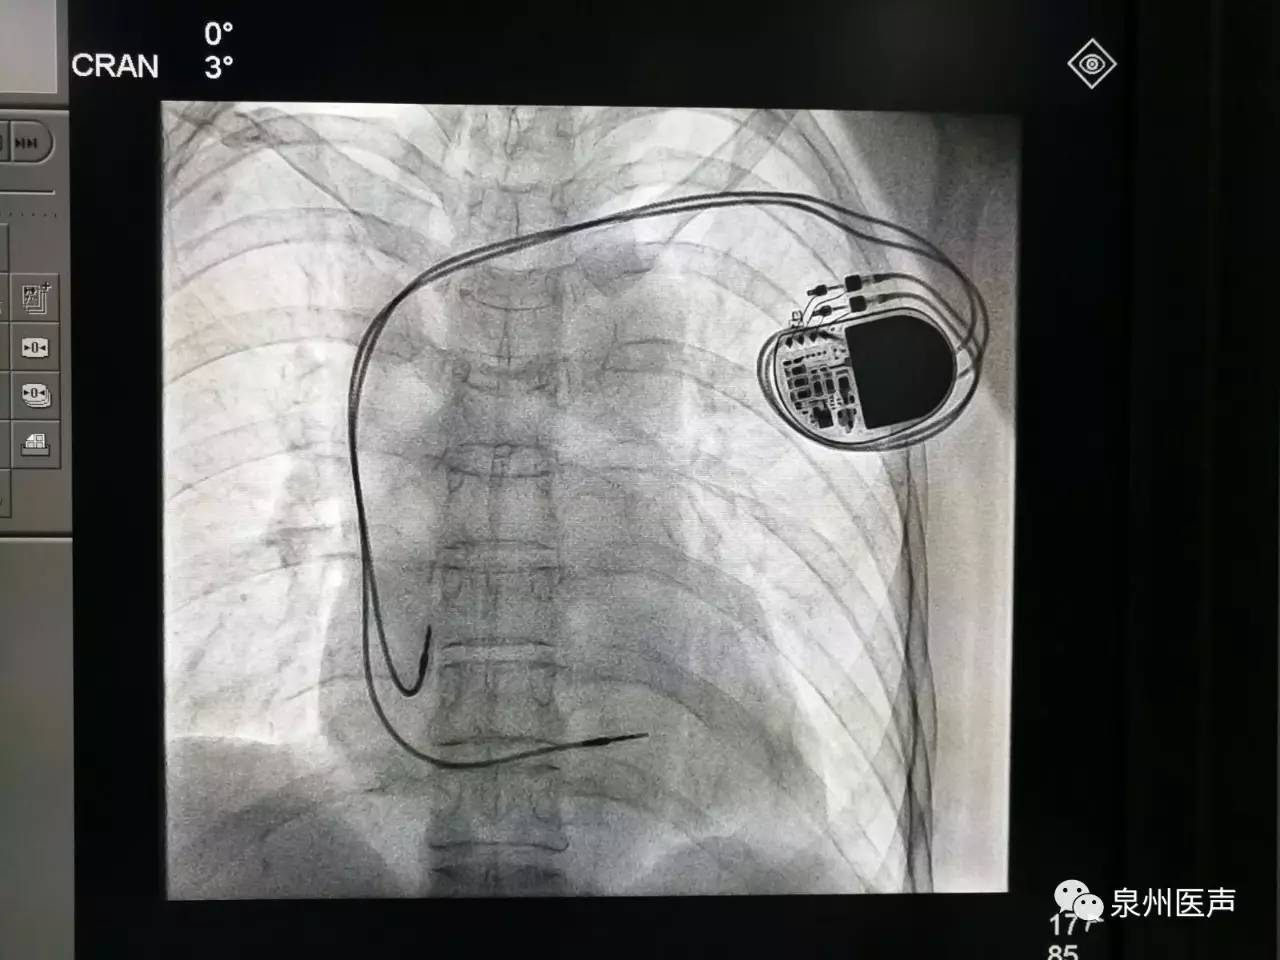

器械之家曾做過專題報(bào)道的“世界最小起搏器”(嬰兒用除外)在經(jīng)過了漫長的中國本土臨床研究后,終于獲得NMPA批準(zhǔn),正式于中國上市!

美敦力公司因可能的電路問題,將召回超過1.3萬個雙腔植入式心臟起搏器。FDA確認(rèn)此次召回為最嚴(yán)重的一類召回,使用該醫(yī)療器械可能或?qū)⒁饑?yán)重健康危害。

心臟起搏器出院的宣教,是心內(nèi)科醫(yī)護(hù)人員不容忽視的一項(xiàng)工作